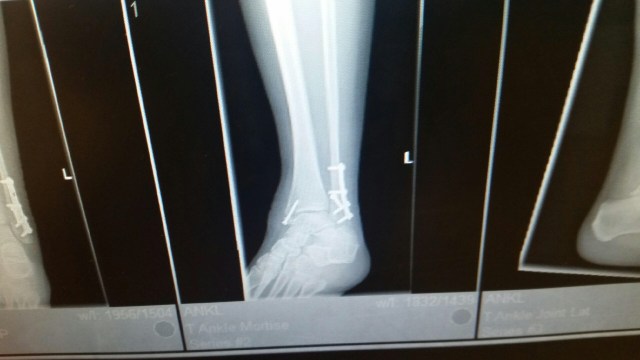

The cast is off! I can’t walk on my ankle for two more weeks, but I can move it a bit. The stitches were removed and I can get the incisions wet and everything! There were twelve stitches on the outside and six on the inside of my ankle. The swelling and bruising isn’t as bad as I thought it would be. It’s kind of scary to have this unprotected ankle, but encouraging to see how much I can move it. I feel like I’m really making progress.